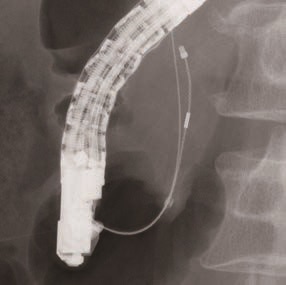

X線不透過チップ

細胞診ブラシの両端とシース先端部の計3ヵ所にX線不透過チップを採用。X線透視下でブラシ部の位置確認が容易になり、目的部位への的確なアプローチをサポートします。